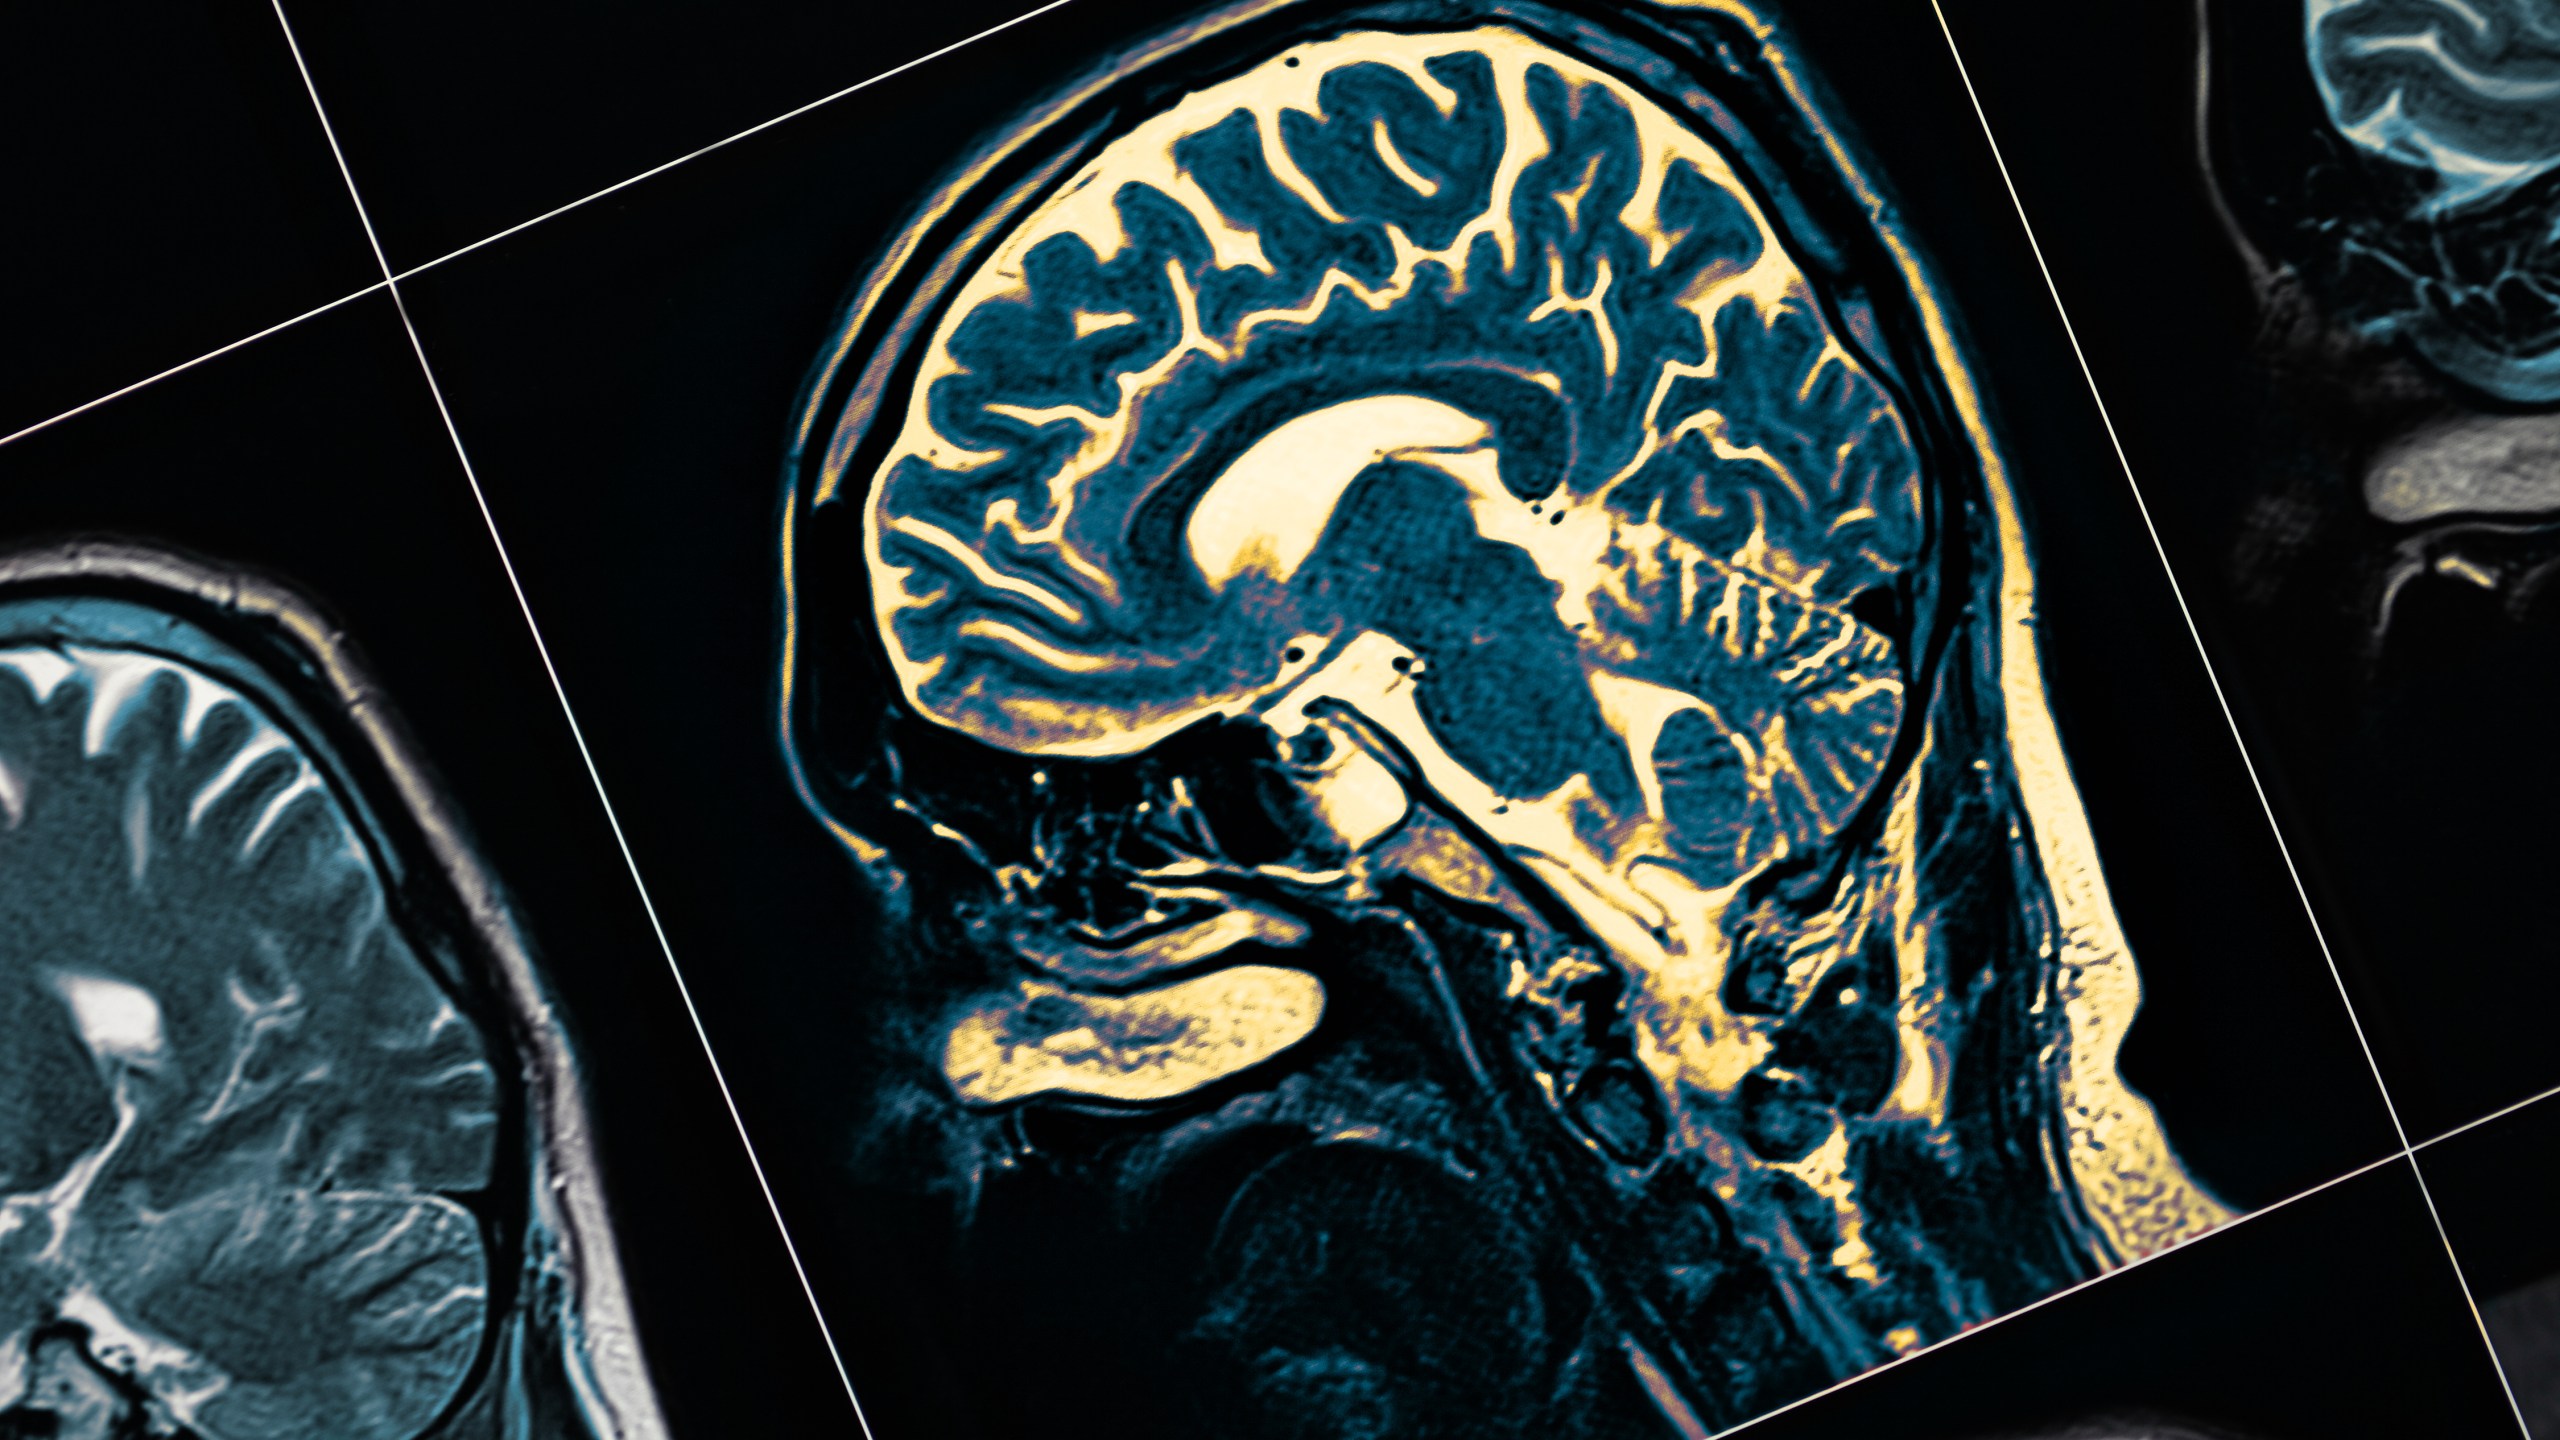

New study examines brain damage in COVID-19 patients

NEW YORK (StudyFinds.org) – Could COVID-19 actually be doing more harm to the human brain than Alzheimer’s disease? A new study reveals older patients contracting COVID have more signs of brain damage than people who develop the neurodegenerative disease.